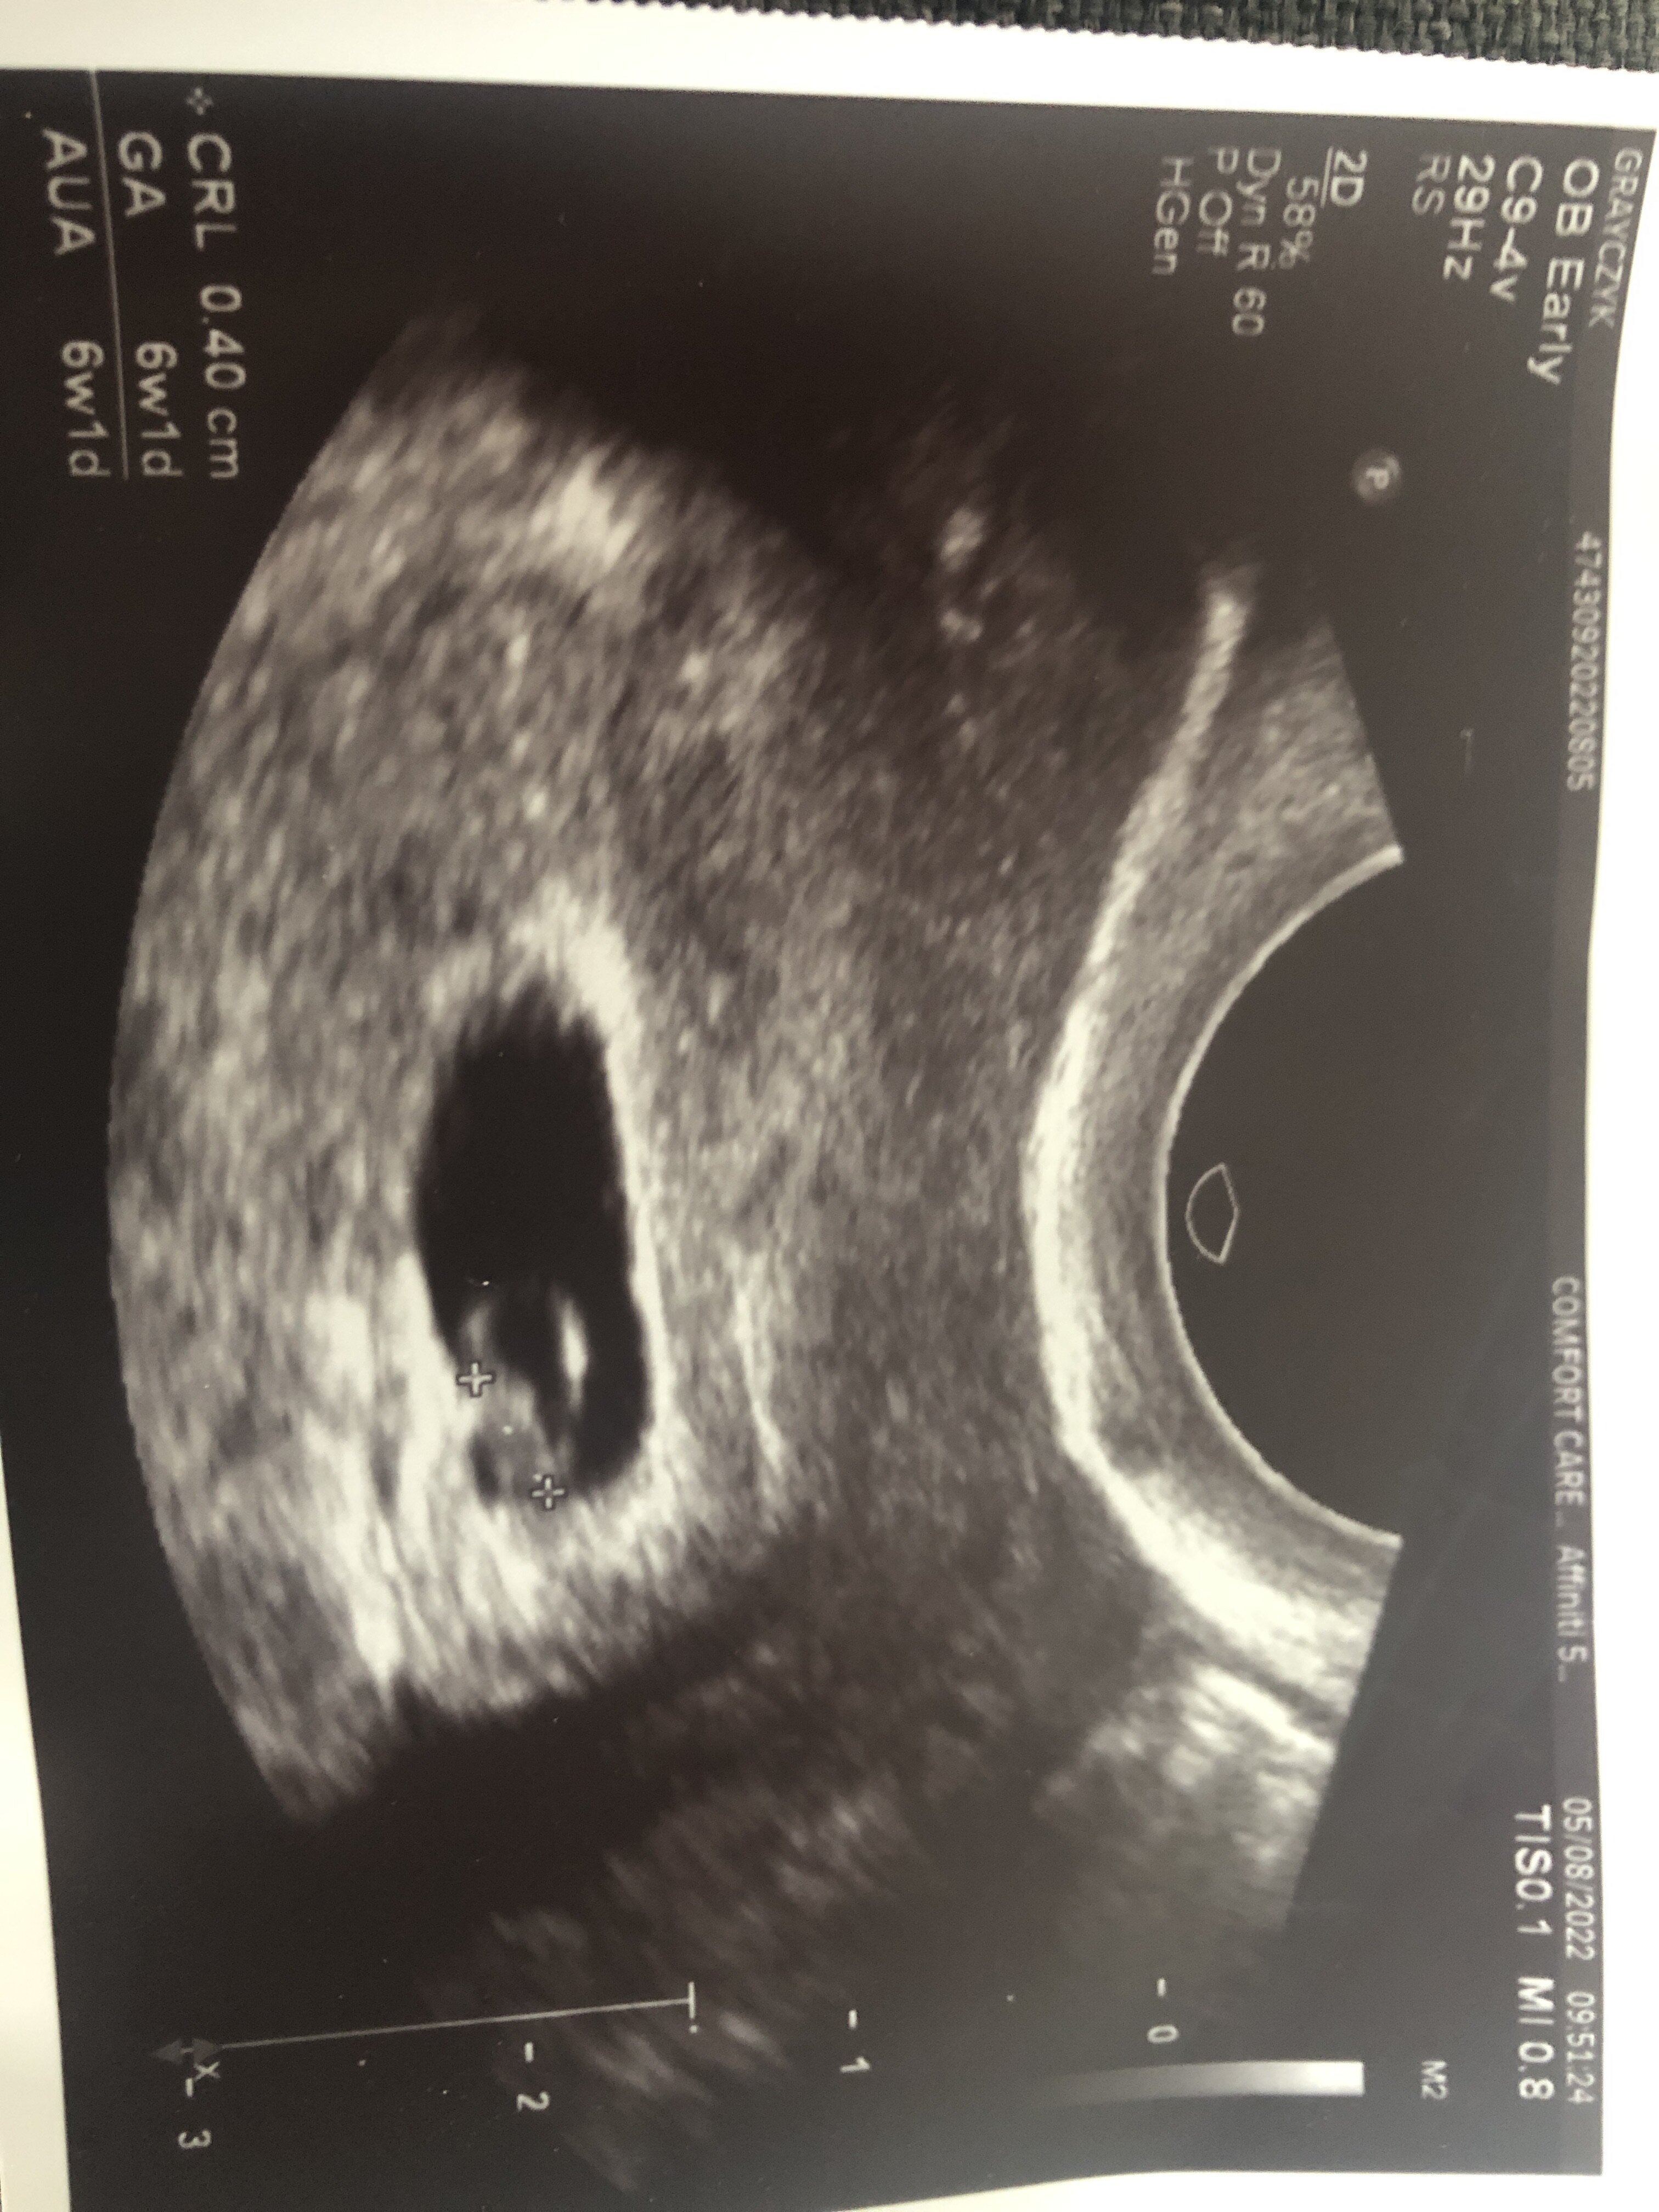

Tak, na zdjeciu mam napisane crl 0.4cm i podobno serce “lekko drgalo”. Ogolnie to byla bardzo szybka wizyta tylko w sumie stwierdzajaca ze nie uroilam sobie tego wszystkiegoO to tak samo jak ja myślałam że jest już 7 tydzień